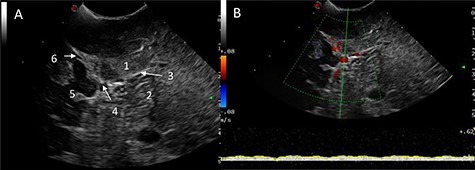

Ultrasound (B-mode) was used to identify the tumour margins, tentorium and venous structures (Fig. 2). Combined with the B-mode, Doppler ultrasound (US) was employed to assess the presence and direction of flow in the right transverse sinus, torcula and superior sagittal sinus. There was presence of blood flow in all these dural venous sinuses, however, the flow within the straight sinus was only unidirectional towards the torcula from the vein of Galen and from the tentorium tributary veins. The unique feature of the intracranial venous sinuses is that blood flow is bi-directional as they lack valves. Hence, this finding suggests there was a degree of venous insufficiency due to obstruction of the venous sinuses engulfed by the meningioma (Fig. 2).

IoUS initial assessment; (A) B-mode image of the surgical field; 1, supratentorial tumour; 2, infratentorial tumour; 3, tentorium; 4, straight sinus; 5, contralateral occipital lobe; 6, falx; (B) triplex Doppler of the straight sinus: combined 2D image with overlay of the colour and pulse wave Doppler demonstrating unidirectional flow from the vein of Galen and the tributary veins of the tentorium.